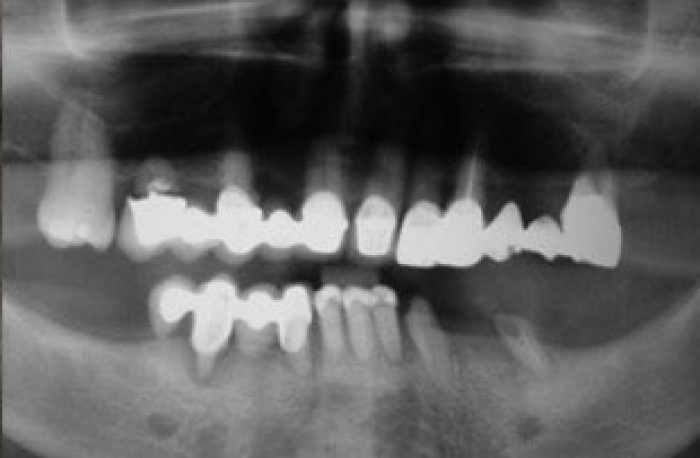

Raio X inicial